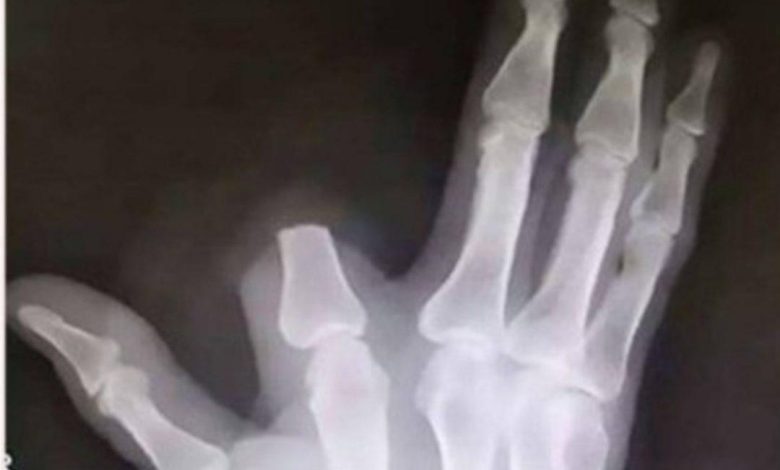

O homem, cuja identidade não foi divulgada, utilizou uma faca para amputar a parte do dedo afetada pela picada. Embora tenha conseguido impedir a disseminação do veneno, a decisão leva a questionamentos sobre a eficácia e segurança deste tipo de abordagem. Especialistas em saúde alertam que amputações não são recomendadas e que o procedimento mais seguro é buscar assistência médica imediata, onde antídotos adequados podem ser administrados.